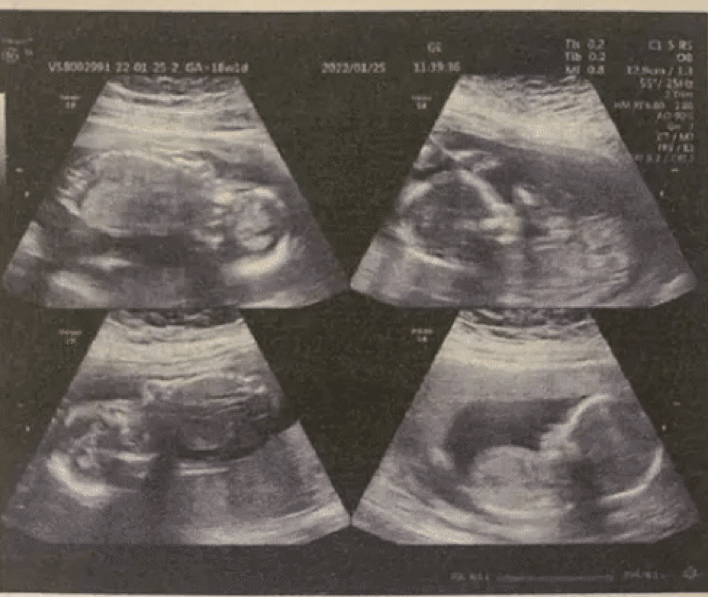

2003年,湖南娄底的易重江,怀孕三个月,肚子就比临产孕妇的还大。旁人都好奇猜测:“可能是双胞胎吧?”

易重江也纳闷,直到医院的检查报告出来,她和家人傻眼了。

“四胞胎,你怀的是四胞胎。”医生五味杂陈地说。医生的话语有些沉重,他们明白这意味着什么。

有关专家按照当时出生概率测算,全世界每出生352.5万人,才可能出现一例全男四胞胎。易重江家确实中大奖了。